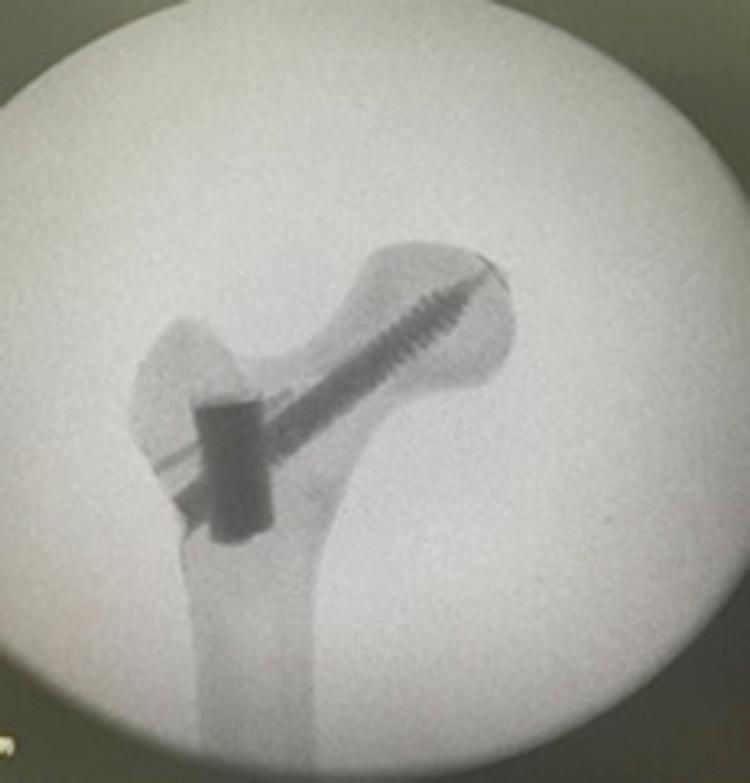

股骨近端髓内钉(PFN)取出后的静态弯曲试验 - 分析

Static bending test after proximal femoral nail (PFN) removal - analysis.

To evaluate, through biomechanical testing, the resistance to and energy required for the occurrence of proximal femoral fracture in synthetic bone after removal of a proximal femoral nail model (PFN), comparing the results obtained with a reinforcement technique using polymethylmethacrylate (PMMA).

Fifteen synthetic bones were used: five units for the control group (CG), five for the test group without reinforcement (TGNR), and five for the test group with reinforcement (TGR). The biomechanical analysis was performed simulating a fall on the trochanter using a servo-hydraulic machine. In the GC, the assay was performed with the PFN intact. In the TGNR and TGR groups, a model of PFN was introduced and the tests were performed in the TGNR, after simple removal of the synthesis material, and in the TGR, after removal of the same PFN model and filling of the cavity in the femoral neck with PMMA.

All groups presented a basicervical fracture. The CG presented a mean of 1427.39 Newtons (N) of maximum load and 10.14 Joules (J) of energy for the occurrence of the fracture. The TGNR and TGR presented 892.14 N and 1477.80 N of maximum load, and 6.71 J and 11.99 J of energy, respectively. According to the Kruskal-Wallis ANOVA, there was a significant difference in the maximum load ( = 0.009) and energy ( = 0.007) between these groups.

The simple removal of a PFN in synthetic bone showed a significant reduction of the maximum load and energy for the occurrence of fracture, which were re-established with a reinforcement technique using PMMA.